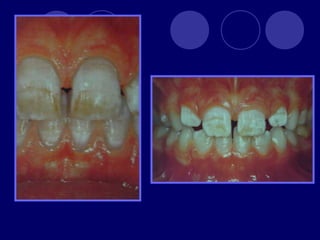

AMELOGENESIS IMPERFECTA  Hipoplásico: Zonas ausentes de esmalte  Afecta más a caras vestibulares  Esmalte: blanco amarillento y marrón claro, consistencia dura, fosas y surcos oscuras, delgado  Hipocalcificado:  Cualitativo  Esmalte frágil, fácil de desprender  Rx: falta de contacto entre dentina, esmalte  Hipomaduro:  Disminución en el contenido mineral  Esmalte blando y rugoso, veteado de blanco a marrón (esmalte en copos de nieve)  Más frecuente en caras vestibulares y dientes superiores

DISPLASIA AMBIENTAL DEL ESMALTE HIPOPLASIA POR INGESTA DE FLÚOR: fluorosis, manchas opacas, esmalte sin brillo(leve=lechoso, graves=amarillo/café) .